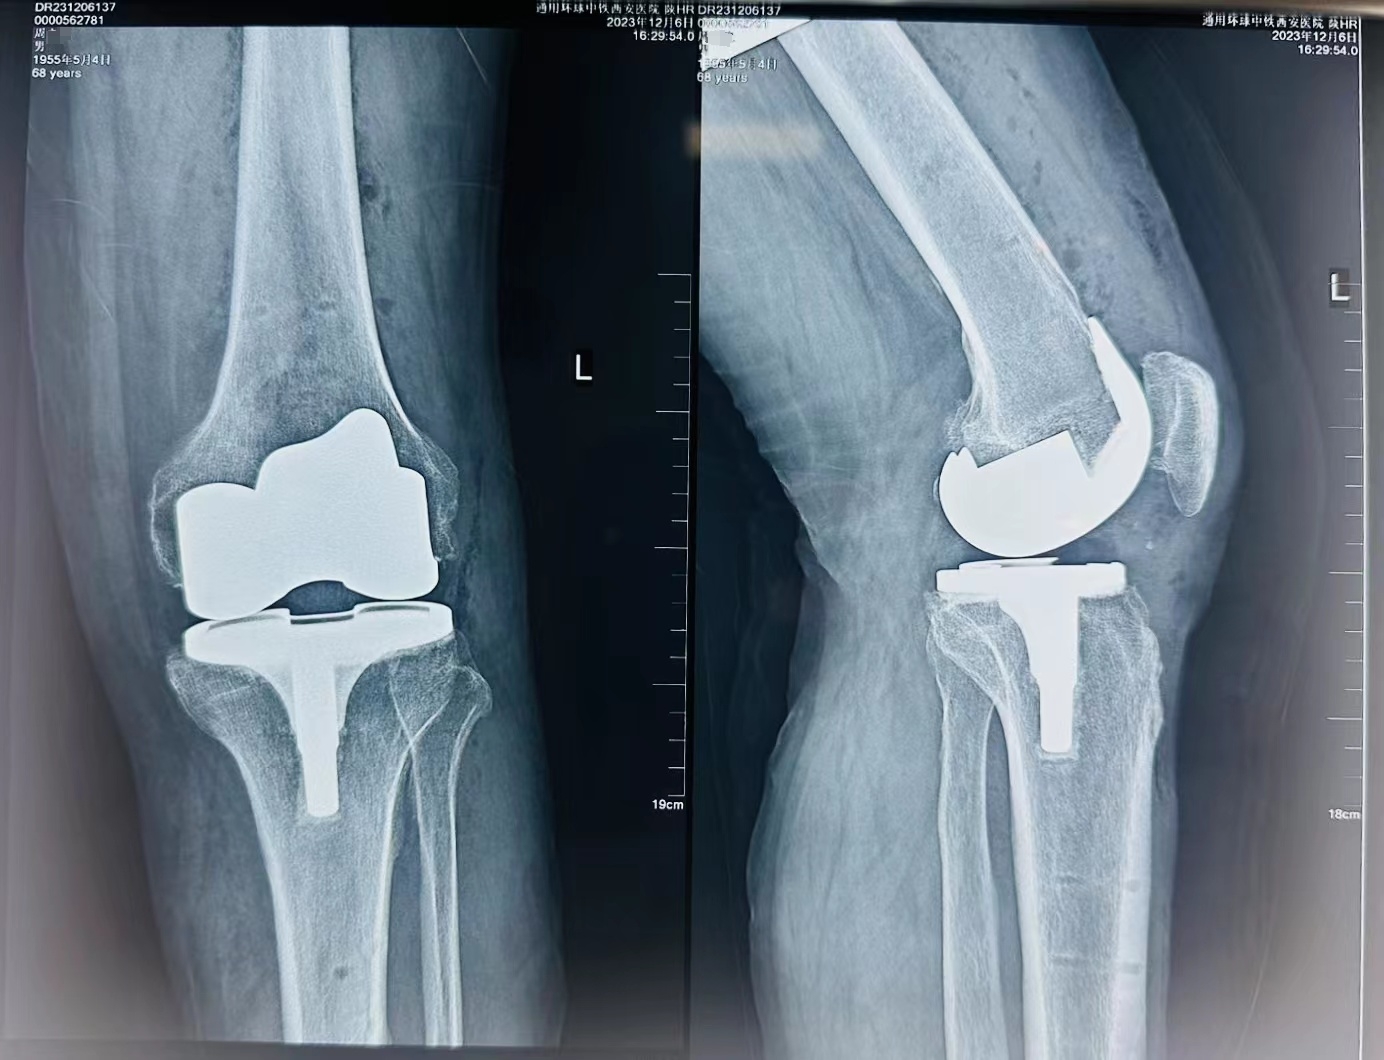

在手麻科(kē)的配合下,手術(shù)順利完成,機(jī)器人(rén)輔助下的截骨操作(zuò)和假體(tǐ)植入都(dōu)實現了毫米的精度,爲延長假體(tǐ)的使用壽命提供了有效的技術(shù)基礎。術(shù)中出血量少,術(shù)後傷口美容縫合護理(lǐ)無管化,術(shù)後4小時周叔即可(kě)進行康複訓練,包括主動和被動活動、行走練習等。

術(shù)後